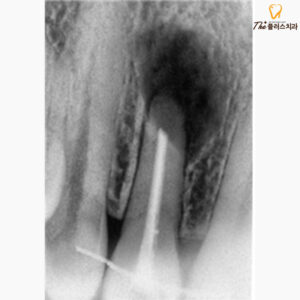

사진은 치근단 절제술을

완료한 후 찍은 사진이며,

염증조직들을 깔끔하게 제거하였고,

치아 끝 부위를 절제한 모습이 관찰됩니다.

뿌리 끝에 세균이 재 감염되지 않도록

끝부분을 MTA라는

특수한 충전 재료를 통해 마무리하였습니다.